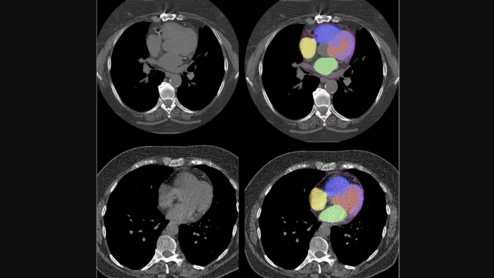

Advanced artificial intelligence (AI) models can evaluate cardiovascular risk in routine chest CT scans without contrast, according to new research published in Nature Communications.[1] In fact, the authors noted, the AI approach may be more effective at identifying issues than relying on guidance from radiologists. Representative non-contrast CT slices for two patients (left), with super-imposed segmentations (right). One artificial intelligence (AI) model was used to segment a cardiac mask.

Two advanced algorithms—one for CAC scores and another for segmenting cardiac chamber volumes—outperformed radiologists when assessing low-dose chest CT scans.